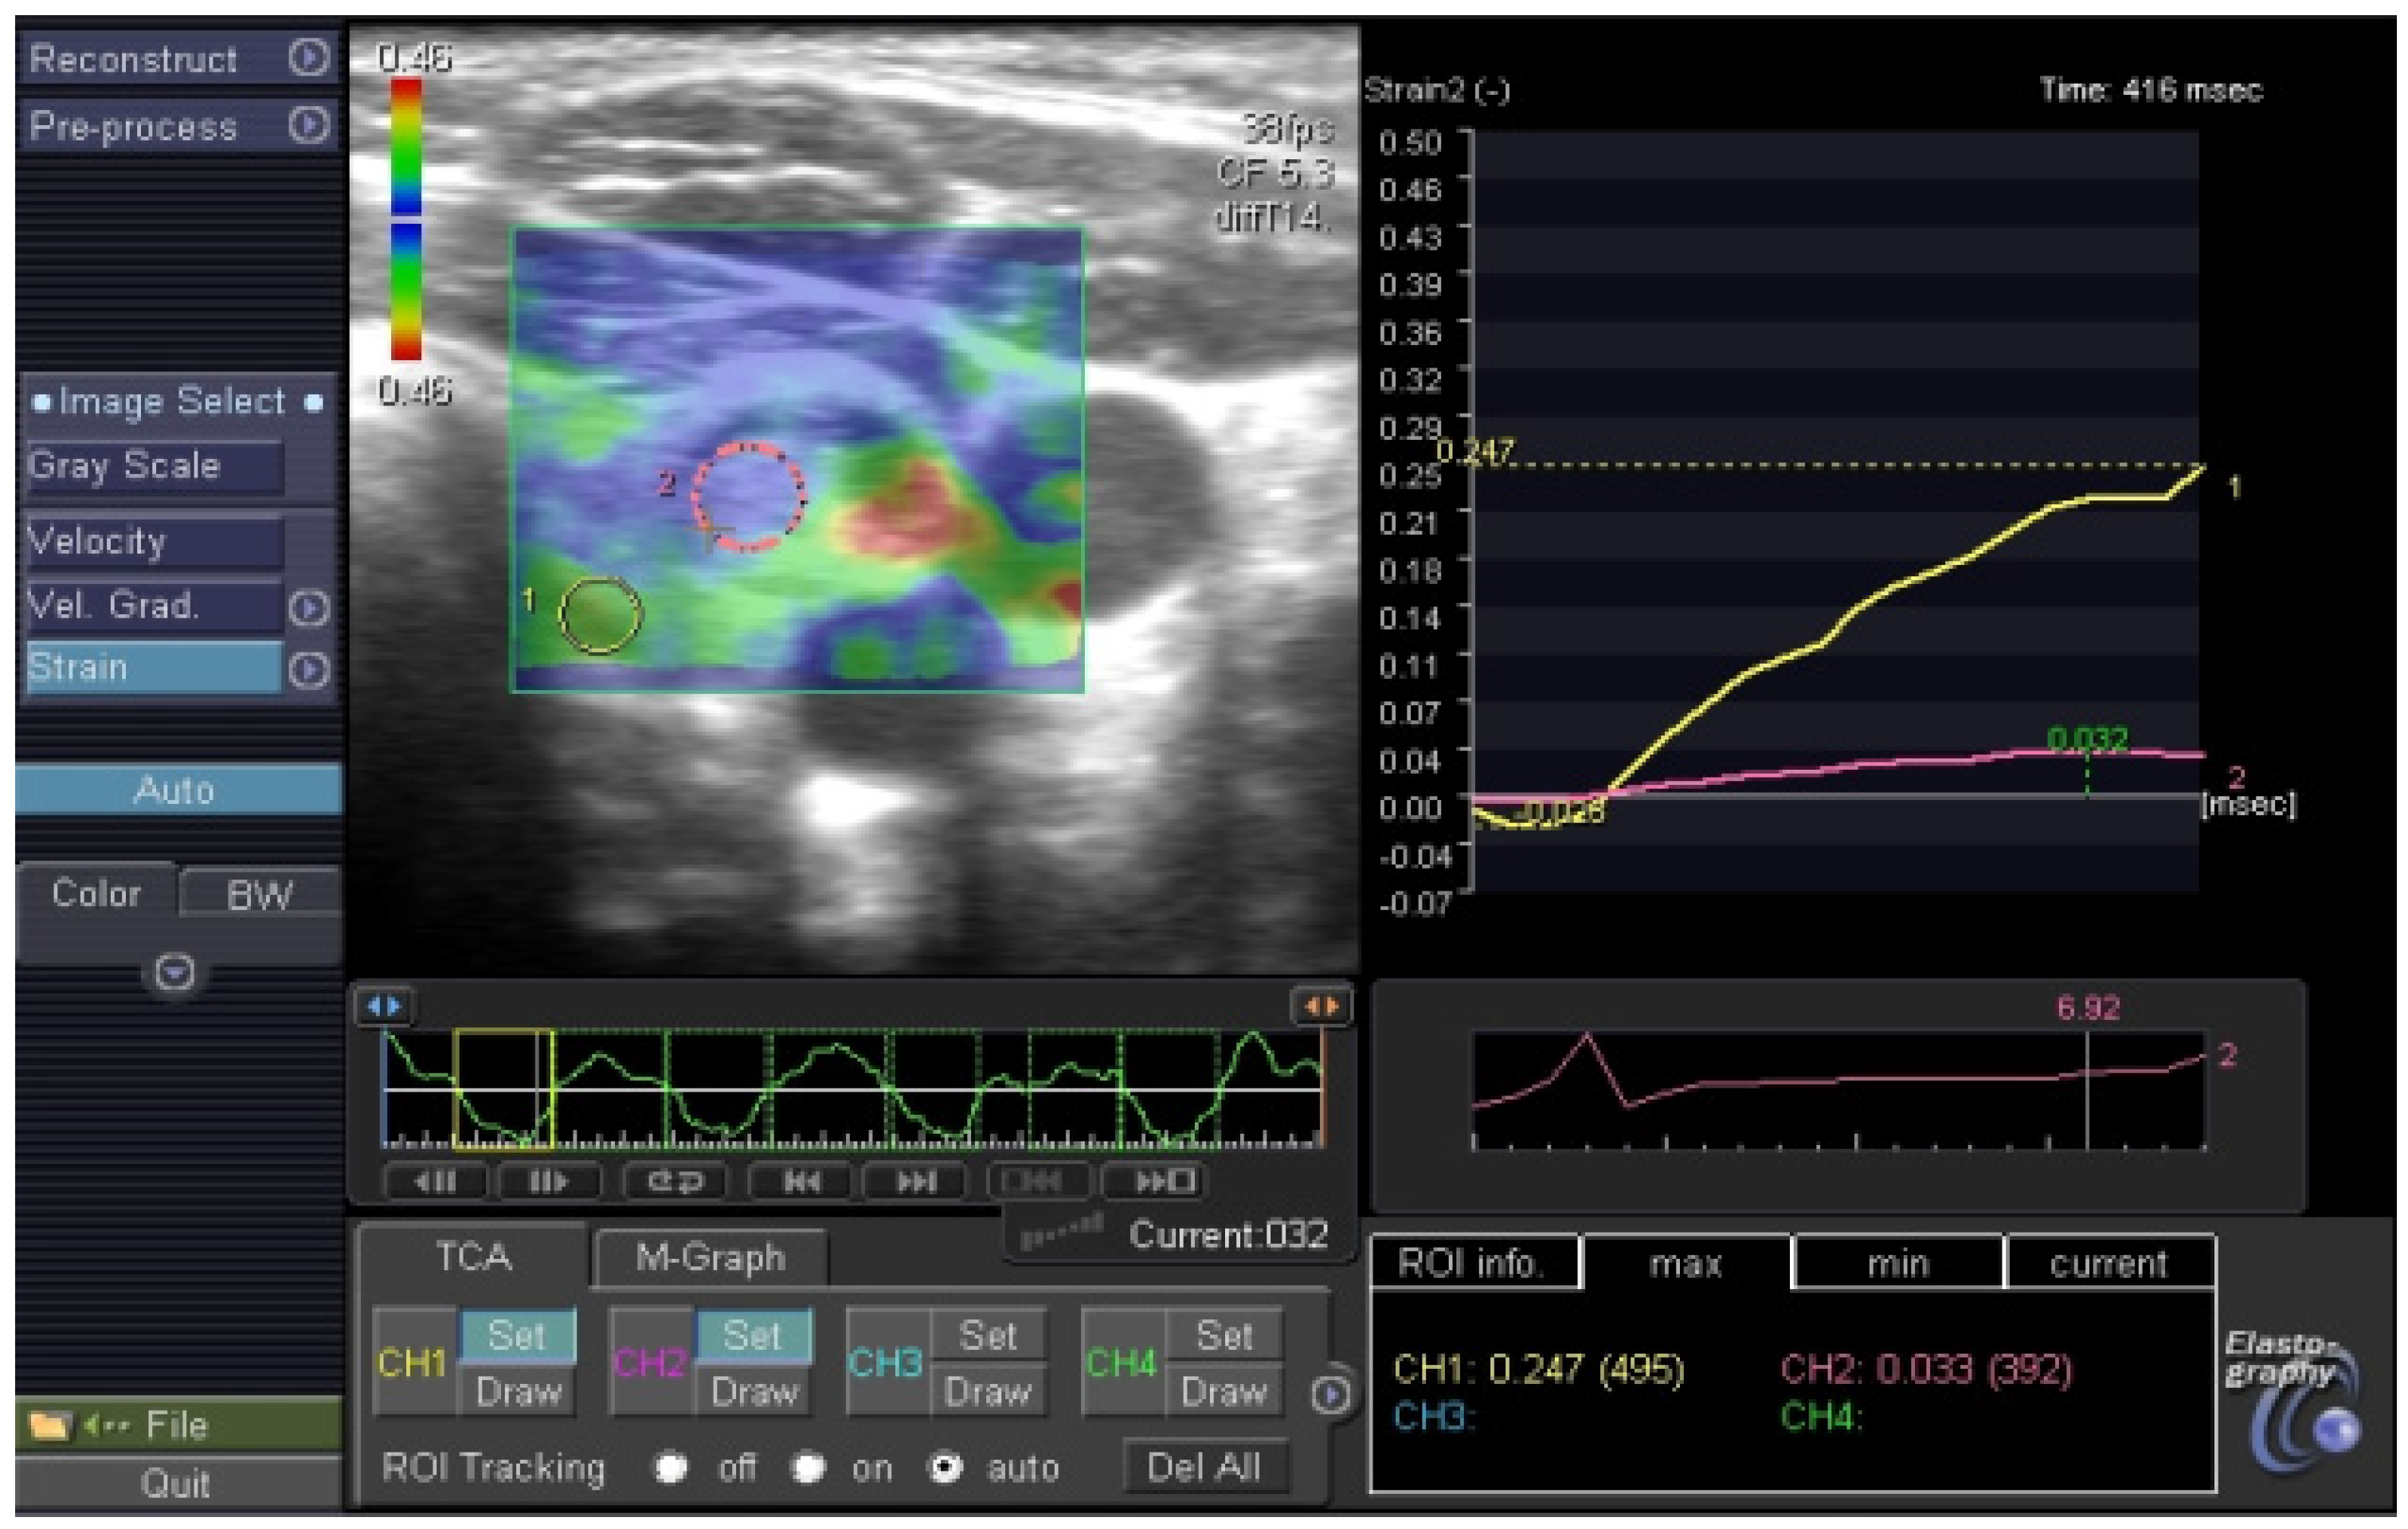

| 1 | F | R | 21 × 15 | 6.3 | VI | high suspicion | U 5b | PTC |

| 2 | M | R | 20 × 17 | 10 | VI | high suspicion | U 5b | PTC |

| 3 | F | R | 6 × 4.5 | 2 | V | high suspicion | U 4d | PTC |

| 4 | F | R | 19 × 17 | nm | V | high suspicion | U 5a | PTC |

| 5 | F | L | 12.5 × 10 | 6 | V | high suspicion | U 5b | PTC |